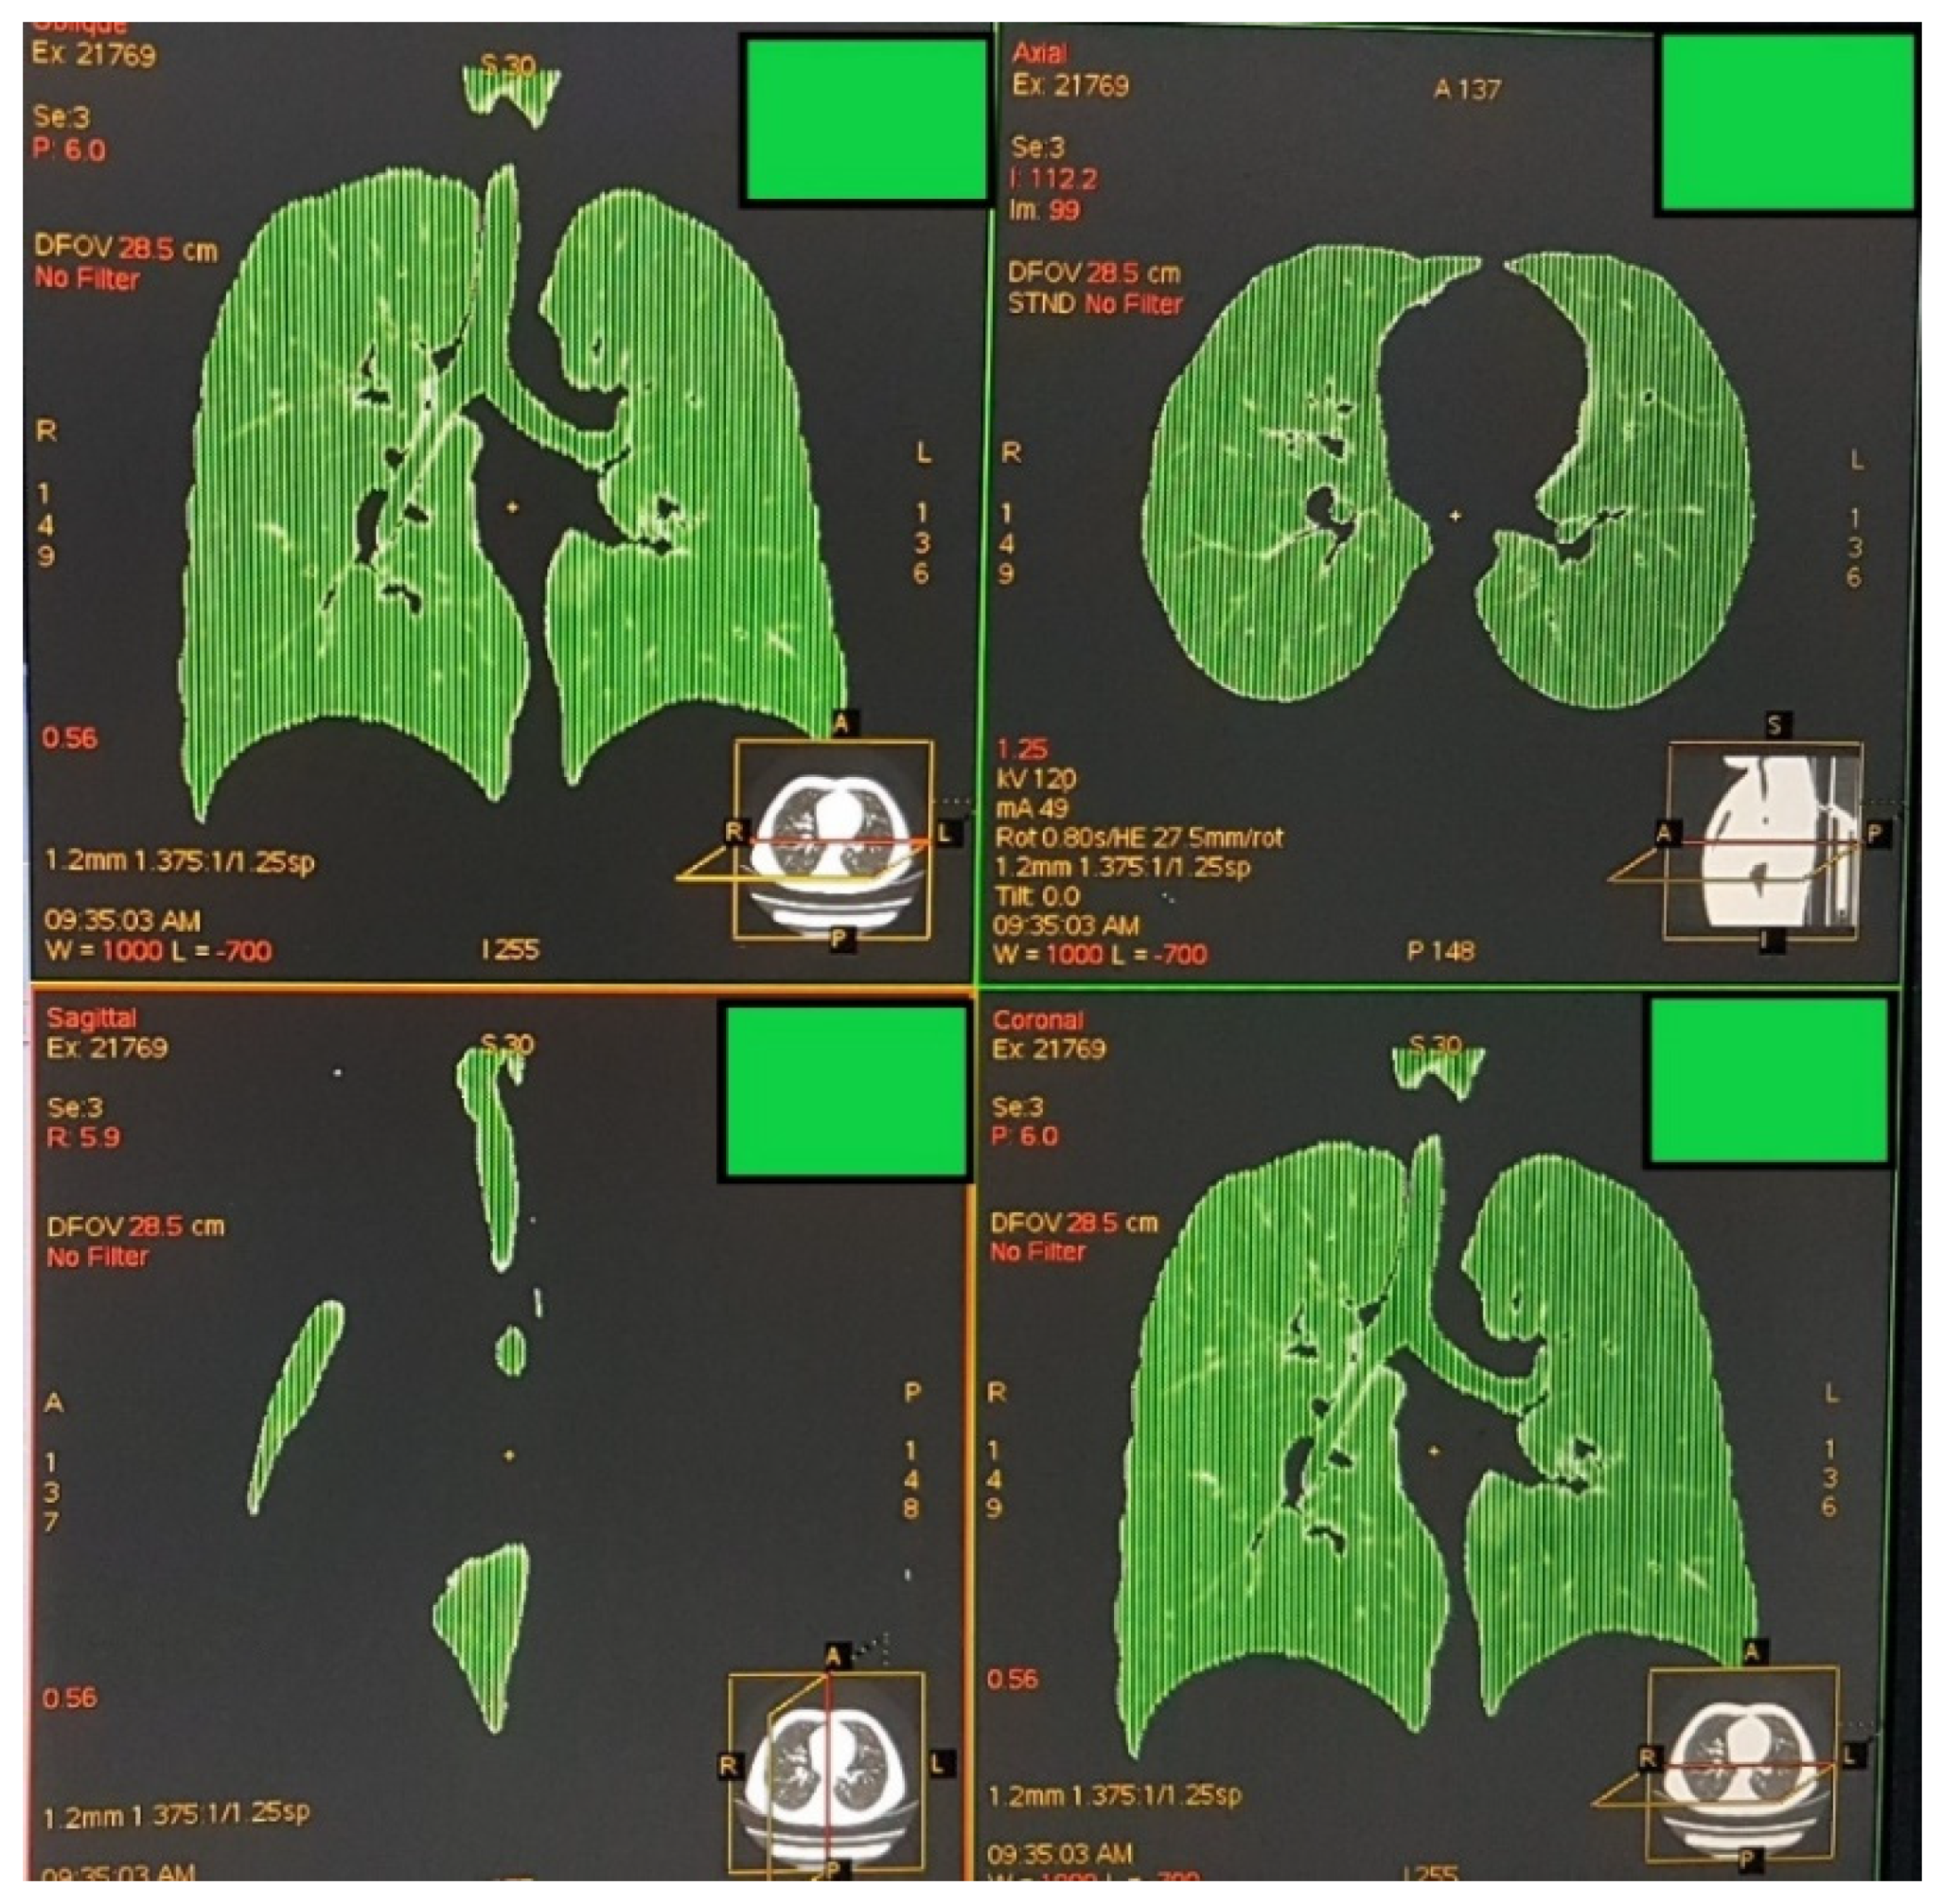

2.2. Image Acquisition, Analysis, and Definition of Attenuation Thresholds

3.2. TLCCT, Mean Lung Attenuation at Full Inspiration and Their Relationship with Age